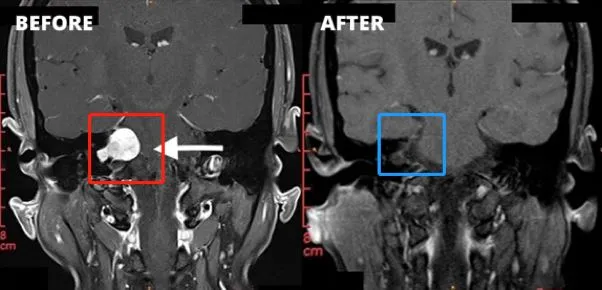

一位43岁男性患者在持续半年的右耳耳鸣后,逐渐出现听力下降、头昏头痛加重,以及面肌抽搐、面部麻木等症状。经检查确诊为听神经瘤,分级已达到Koos 3级、Samii T4a级,属于中大型肿瘤。面对这一结果,他陷入了两难:不手术,肿瘤持续生长,压迫神经的风险不断升级;选择手术,又担心术后出现面瘫或失聪。

经过充分评估,患者最终决定接受手术治疗。在术中神经电生理监测的全程护航与主刀医生丰富手术经验的支撑下,肿瘤被完全切除,术后既没有出现面瘫,听力功能也得到了有效保留。术后两周的面神经功能评估达到了House-Brackmann最高的1级标准,术后9个月随访显示,患者生活已完全恢复正常,未留下任何神经功能障碍。